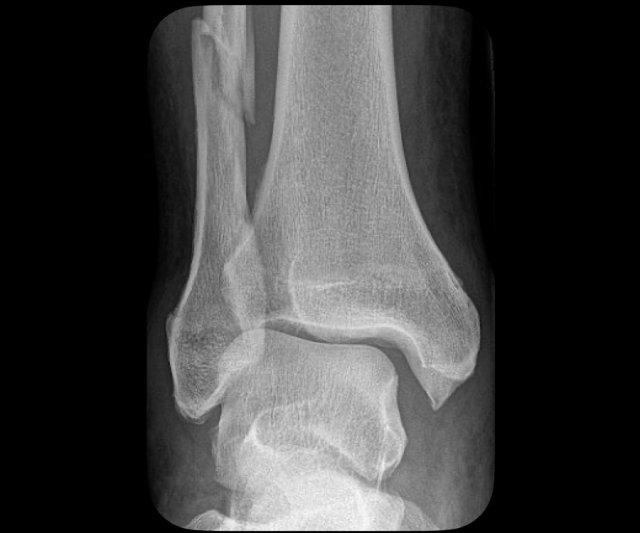

Giai đoạn 1

Đây là hình ảnh điển hình của gãy xương bứt rời hoặc gãy do lực kéo giật ở mắt cá ngoài.

Mảnh xương bứt rời khá lớn. Thông thường hơn, mảnh bứt rời có kích thước nhỏ.

Đây là gãy xương Weber A giai đoạn 1, có tính ổn định.